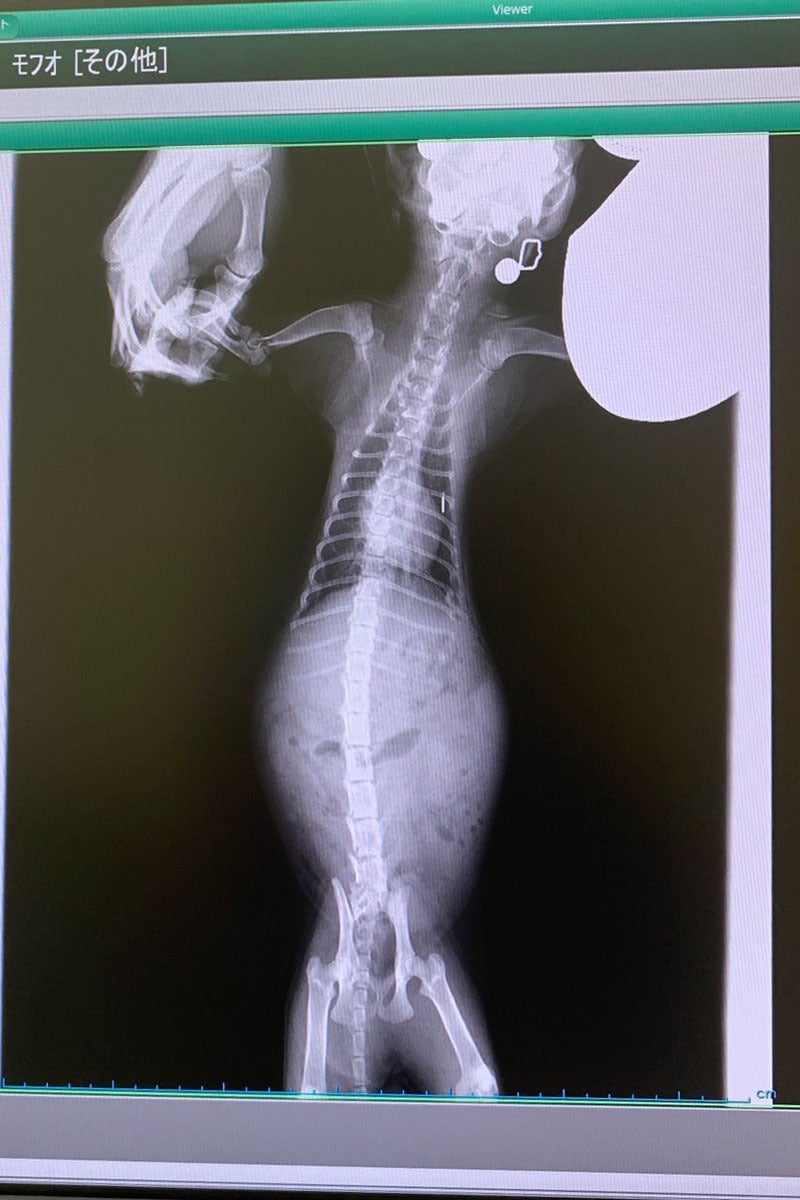

もふおは腹水が溜まるウェットタイプと、

腹部に肉芽腫が発生するドライタイプ、両方を発症していることが分かりました。

進行状況としては中期の状態で、

正直あまり良い状態ではありませんでしたが、